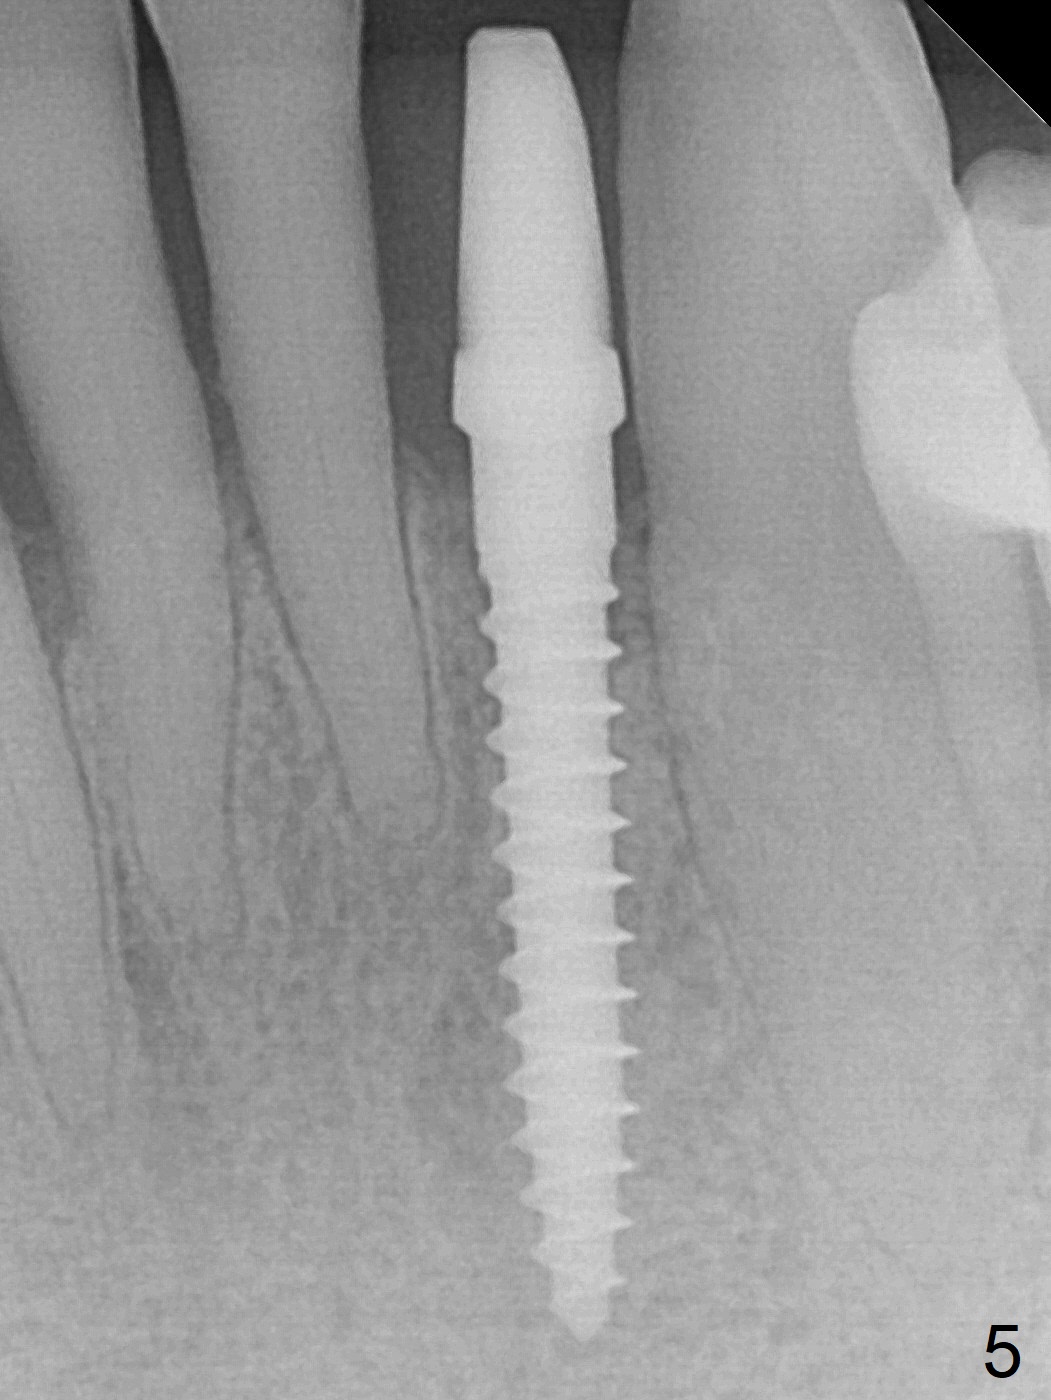

The tooth #23 is going to be extracted because the patient cannot masticate normally with mobility (Fit.1). The gingival depth is measured 2-4 mm after extraction. The 1st intraop PA taken with 1.2 mm drill for 16 mm shows the mesiodistal width is 5.11 mm (Fig.2); a 2.5x14(2) mm 1-piece implant is placed with >35 Ncm (Fig.3 with allograft placed). Following abutment preparation, an immediate provisional is fabricated to close the socket (Fig.4 P). There is no bone loss (Fig.5) or gingival inflammation (Fig.6 after reprep) 3 months postop. The narrow implant (2.5 or 2.0 mm) is indicated in the narrow edentulous space. The distal crest seems to be reduced in density and lower in height 1 year 7 months (Fig.7) and 1 year 11 months (Fig.8) post cementation. The severity does not worsen probably related to use of water pik. The crown looks bulky probably due to too large the abutment and too buccal placement of the implant (Fig.9, 10, as compared to Fig.1). A 2 mm implant may help?